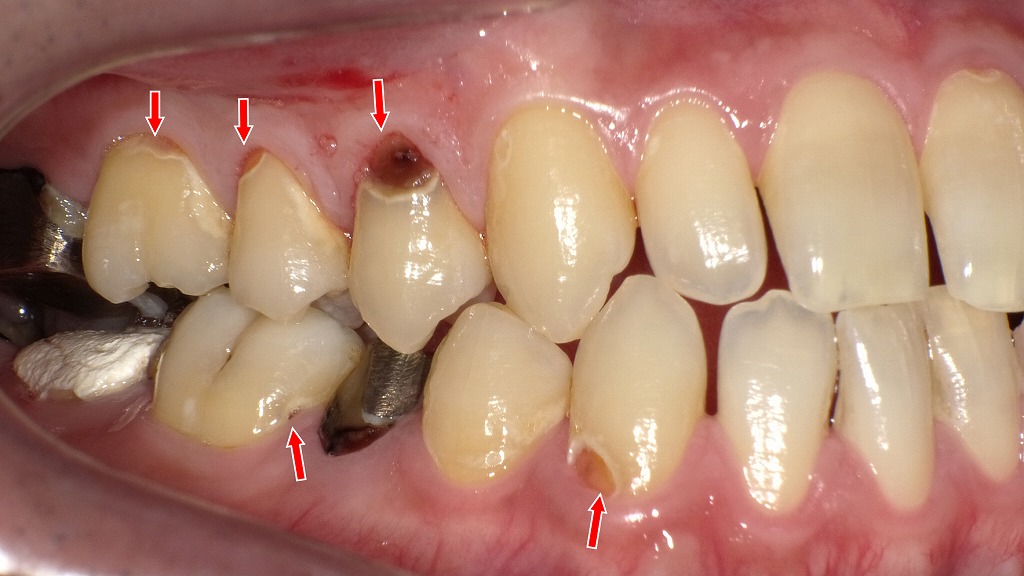

前歯から奥歯まで広がる重度の歯頸部う蝕症例

歯と歯ぐきの境目(歯頚部)に発生した虫歯の症例です。治療前には、歯頚部う蝕や既存のコンポジットレジン充填の変色、二次カリエスが認められました。虫歯を除去した後、コンポジットレジン充填により形態と審美性を回復しています。今回治療した部位以外の虫歯についても、順次コンポジットレジン充填を行い、口腔内全体の健康維持を図っていきます。